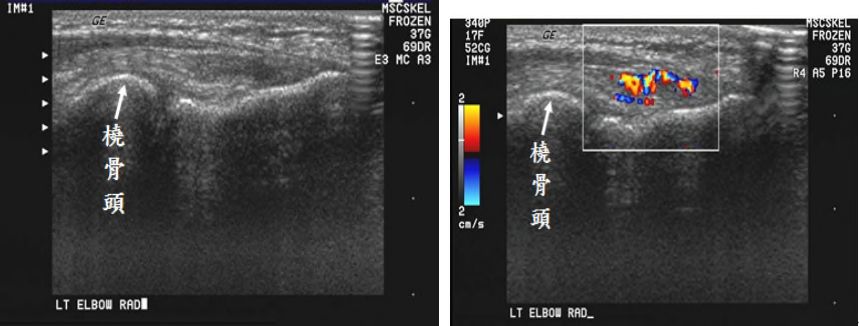

73.49 歲男性病人,主訴左肘關節疼痛,尤其在橈側(radial side),灰階及彩色杜卜勒超音波檢查如圖,最可能診斷為何? (A)高爾夫球肘(golfer's elbow) (B)網球肘(tennis elbow) (C)橈側側副韌帶部分斷裂(partial tear of radial collateral ligament) (D)臂橈肌部分斷裂(partial tear of brachioradialis muscle)